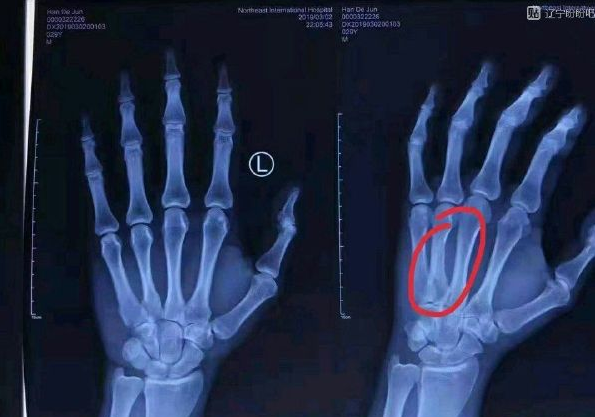

北京时间3月4日,辽宁中锋韩德君今日在北京积水潭医院对伤手再次进行了诊断,并最终敲定了治疗方案。据消息称,韩德君对骨折的手掌进行了石膏外固定,他的伤手需要6周时间恢复。

在上轮对阵广厦的常规赛中,韩德君在对抗中戳伤了手部。赛后经过诊断确定是骨折。随后,辽宁队决定让韩德君前往北京咨询专家的意见,确定治疗方式。网上也出现了韩德君手部的X光片。